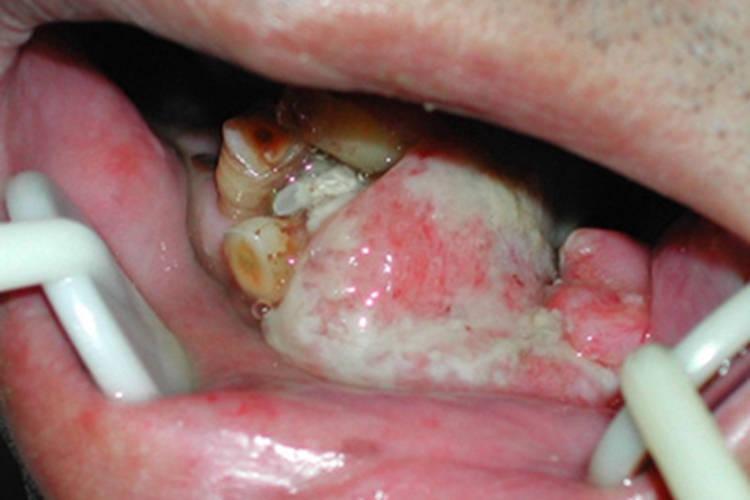

牙龈瘤在牙龈上可长出一个很大的肿块,肿块表面出现糜烂,覆盖一层灰白色的假膜,假膜脱落可出现糜烂面,邻近的牙齿可出现疼痛,叩痛明显,还可出现松动移位。